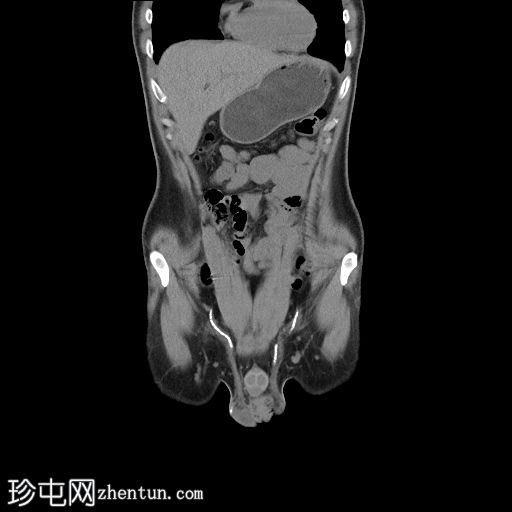

冠状位

平扫

双侧肾盏可见多发性致密结石

左侧近端输尿管可见一枚致密结石。无相关反压改变。

双侧输尿管走行及管径均属正常。

双侧输精管可见近乎对称的钙化。